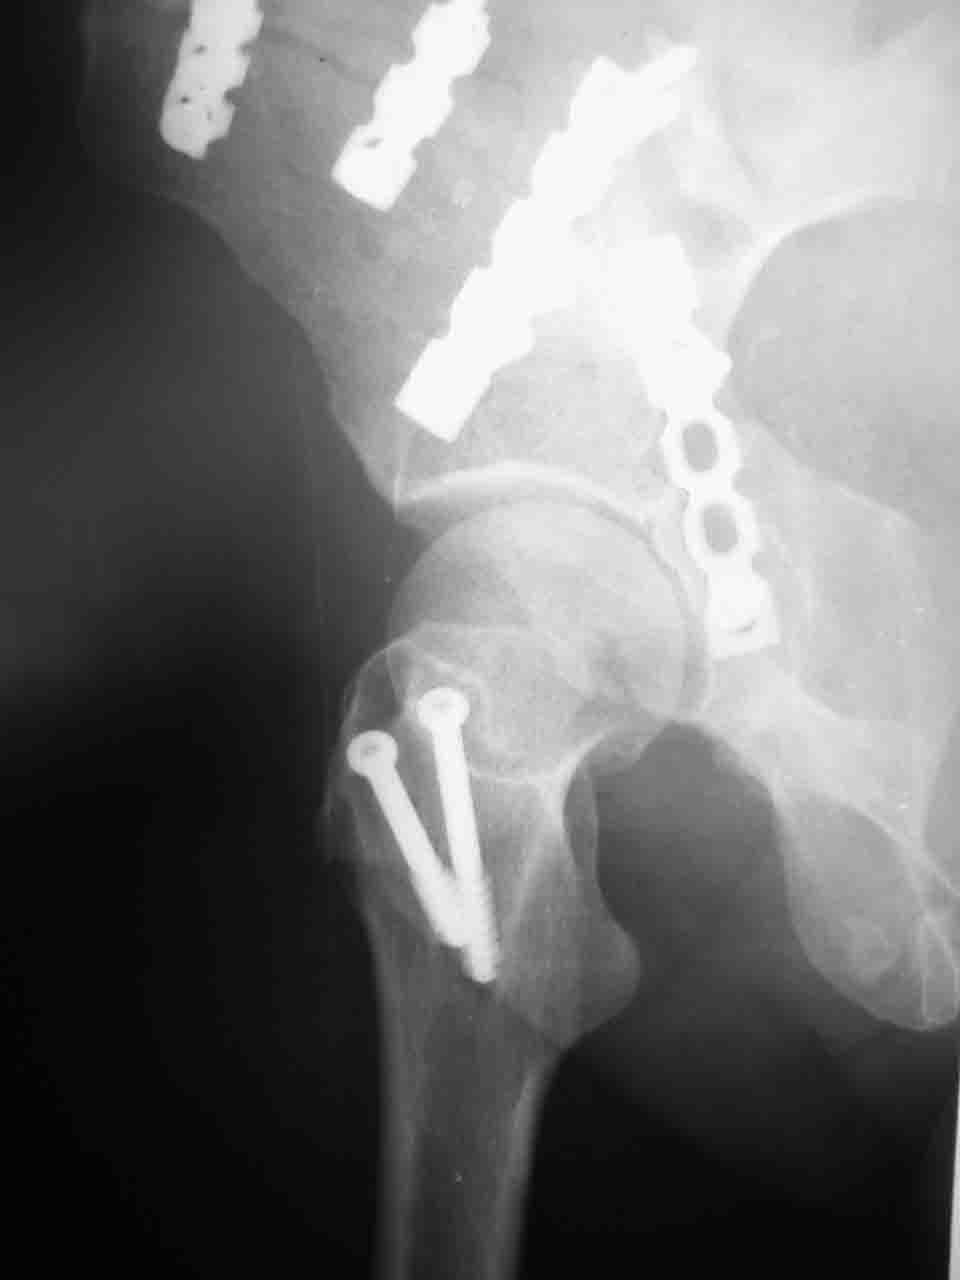

Спасибо за комментарии и рекомендации. Откровенно говоря, больного я прооперировал на прошлой неделе, через 5 дней после аварии и проблем с ним пока никаких нет, на удивление при достаточно обширной диссекции (илиофеморальный доступ) болей практически нет, так что больной самостоятельно садится в кровати, выполняет активные движения в оперированном суставе, сгибая до 60 градусов пока, далее с ассистенцией.

Причиной обращения к сообществу были возникшие непосредственно после операции сомнения и разочарования полученным качеством репозиции: а надо ли было трогать перелом вообще, репозиция передней колонны технически была очень сложна для меня, хотя реконструкции была в той же последовательности, что Д-р А.В.Рунков рекомендовал, в какой-то момент безуспешных манипуляций стал думать о *вторичной конгруэнтности*, которую не так давно обсуждали на

форуме и скелетном вытяжении. С репозицией и фиксацией задней колонны и отдельно задне-верхней стенки впадины проблем не возникло. Послеоп. Рг граммы в приложении. Если возникнут какие-либо дополнения или поправки - был бы признателен.

А какой отдел вертлужной впадины более важен передний или задний? Чем был обусловлен выбор доступа к суставу? Проще говоря, почему вы пошли передним доступом на двухколонный перелом? Мне понятны ваши сомнения, когда не удется сделать все что хотелось бы. В данном случае доступ должен быть чрезвертельным боковым (как и советовал Рунков) или двумя доступами.

Илеофеморальный доступ не совсем передний и сравнительно с илеоингвинальным, и Кохера-Лангенбека открывает весь наружный таз кроме самых передних отделов лонных костей, фиксацию которых я не ставил в задачу. Обширность диссекции, большая длительность операции и более высокий риск гетерооссификации - отрицательные моменты в обмен на возможность легче ориентироваться.